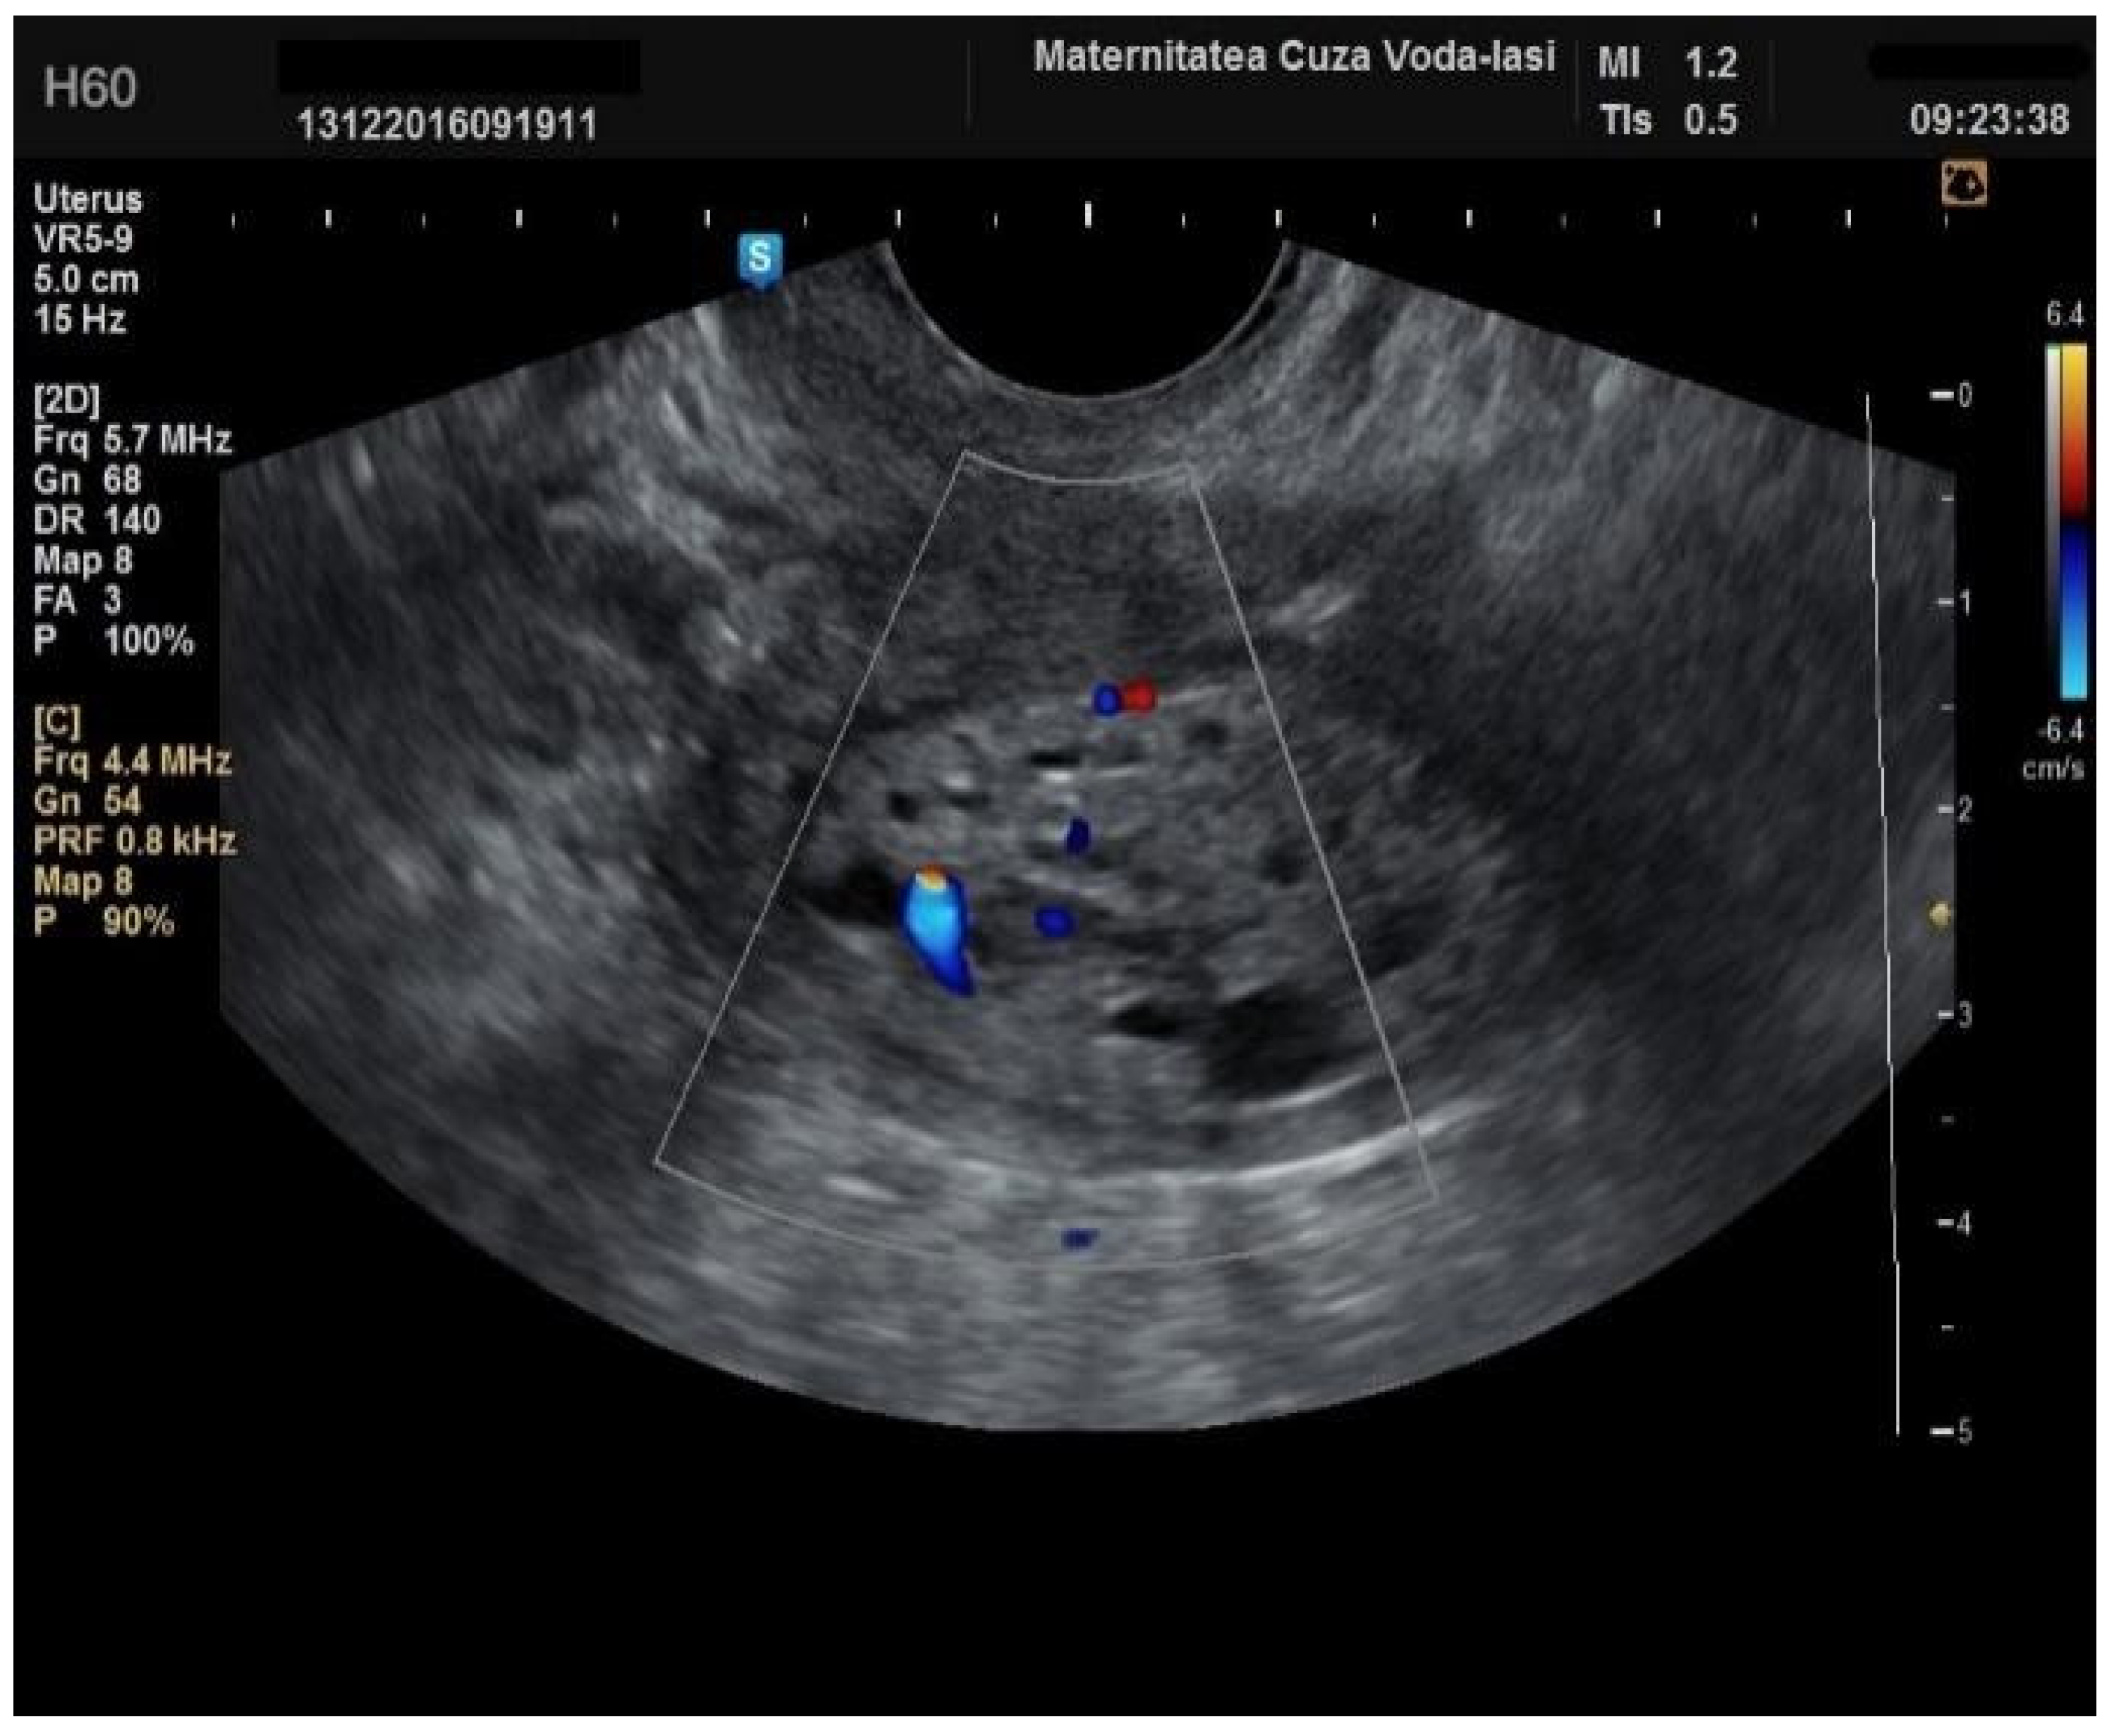

Furthermore, color Doppler imaging proved valuable in more accurately determining myometrial invasion. The predominant feature of blood vessels in endometrial cancer was the presence of scattered vessels (Figure 10), which demonstrated a sensitivity of 50% (95% CI: 0.2152 to 0.7848) and a specificity of 94.74% (95% CI: 0.8563 to 0.9819). Additional vascular aspects indicative of endometrial cancer were the presence of vessels with various branches (Figure 11) and color splashes (Figure 12).

Figure 12. Color Doppler imaging for assessing endometrial invasion in endometrial cancer: presence of color splashes.